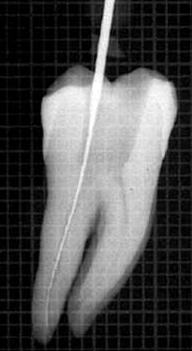

El resultado final debe ser una cavidad de acceso que permita a los instrumentos endodóncicos alcanzar los orificios de entrada de los conductos sin interferencia alguna y lo más rectilíneamente posible. Ver imágenes derecha.

Se debe rectificar la cámara para que la lima acceda en forma vertical "A" para ello se utiliza la fresa SX  ó Pre RaCe

Acceso vertical con lima 10 manual